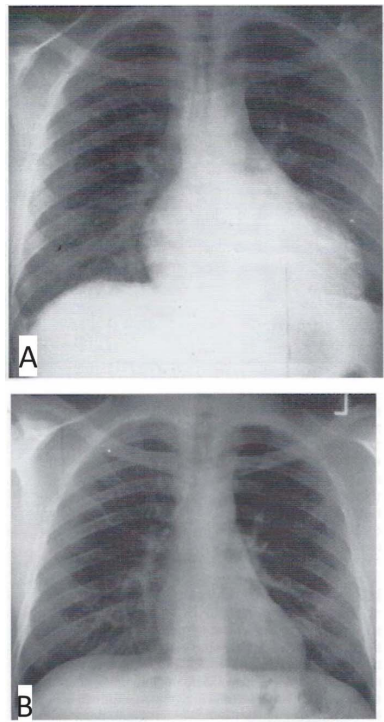

Um homem de 34 anos de idade, sabidamente portador de infecção pelo vírus da imunodeficiência humana (HIV), apresentou início recente de febre e dispneia. O exame físico revelou a presença de febre, taquicardia, turgência de jugular, atrito pericárdico e hepatomegalia. Realizou uma radiografia de tórax, que é mostrada na parte A da figura, obtendo um diagnóstico a partir da obtenção do líquido pericárdico e de uma amostra de biópsia pericárdica. O líquido pericárdico era caracterizado por um nível elevado de adenosina desaminase. A radiografia de tórax mostrada na parte B foi obtida três semanas após o início da terapia apropriada.